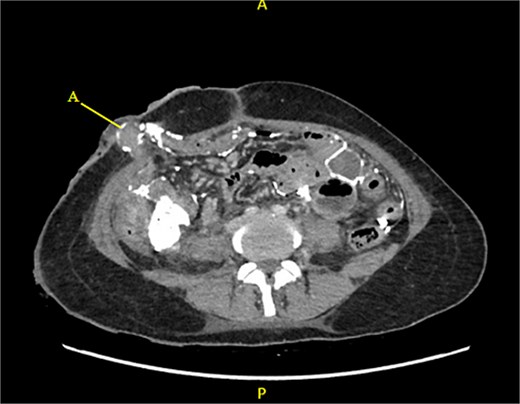

Contrast-enhanced CT of the abdomen and pelvis revealed extensive barium extravasation outlining the peritoneal cavity, accompanied by pneumoperitoneum (Fig. 3). Two barium-outlined, walled-off intra-abdominal collections were identified: one located anterior to the lower pole of the left kidney and the other in the pelvis, anterior to the rectum (Figs 4 and 5). Due to significant barium-related imaging artifacts, the precise site of bowel perforation was not identified. A diagnosis of peritonitis secondary to barium spillage was established, with associated intra-abdominal collections.

Rectum (A) large barium containing pelvic collection anterior to the rectum, the drain was placed in this collection (B).